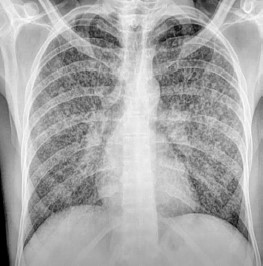

Diagnosticado com HIV/AIDS, neurotuberculose e tuberculose pulmonar miliar. Seguem exames de imagem.